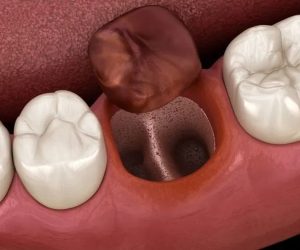

通常、抜歯後には、抜歯した穴(抜歯窩)に血液が溜まり、血の塊(血餅:けっぺい)というゼリー状のかさぶたが形成されます。

この血餅が、傷口を細菌や外気から守り、骨や歯ぐきが再生するための足場となります。

ですが、何らかの原因により血餅が正常に形成されない、あるいは剥がれて脱落してしまうことで、抜歯窩の底にある顎の骨がむき出しになり、外気や唾液、細菌に触れて炎症を起こします。この状態を「ドライソケット」と呼びます。

抜歯窩の状態

血餅がなくなり、穴の中が白っぽい骨が見えている状態になることがあります。